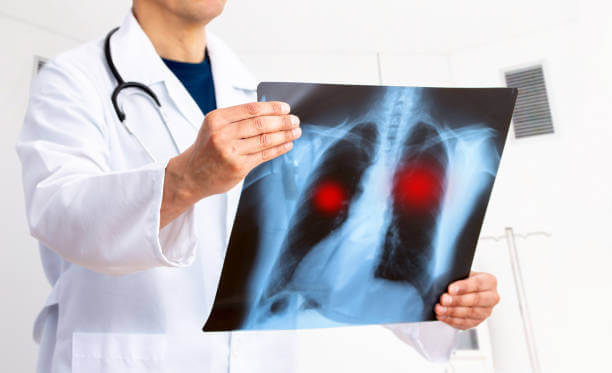

검사과정

폐부종의 진단을 위해 다양한 검사가 수행될 수 있습니다. 이는 폐 기능 평가, 원인 파악 및 평가, 합병증 확인 등을 위한 목적으로 진행됩니다.

원인 파악 및 평가: 폐부종의 원인을 확인하기 위해 심장 초음파, 심전도, 혈액 검사 등이 수행될 수 있습니다. 이는 심장 기능, 혈액 순환 상태, 심장질환 여부 등을 평가하는데 사용됩니다.

합병증 확인: 폐부종과 관련된 합병증 여부를 확인하기 위해 흉부 X-선, CT 스캔, 혈액검사 등이 수행될 수 있습니다. 이는 폐 이외의 다른 기관과 조직의 상태를 확인하는데 도움을 줍니다.